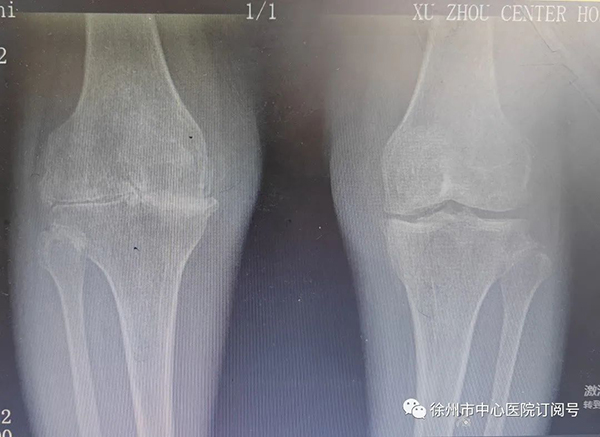

(手術(shù)前后影像對比)

術(shù)中,發(fā)現(xiàn)患者股骨、脛骨、髕骨軟骨廣泛剝脫,髕骨關(guān)節(jié)軟骨下骨裸露,邊緣有大量骨贅形成,內(nèi)外側(cè)半月板退變,邊緣毛糙,關(guān)節(jié)腔內(nèi)可見大量淡黃色滑液,滑膜增生肥厚。那鍵憑借豐富的臨床經(jīng)驗,將患者右膝關(guān)節(jié)全部置換,手術(shù)順利完成。